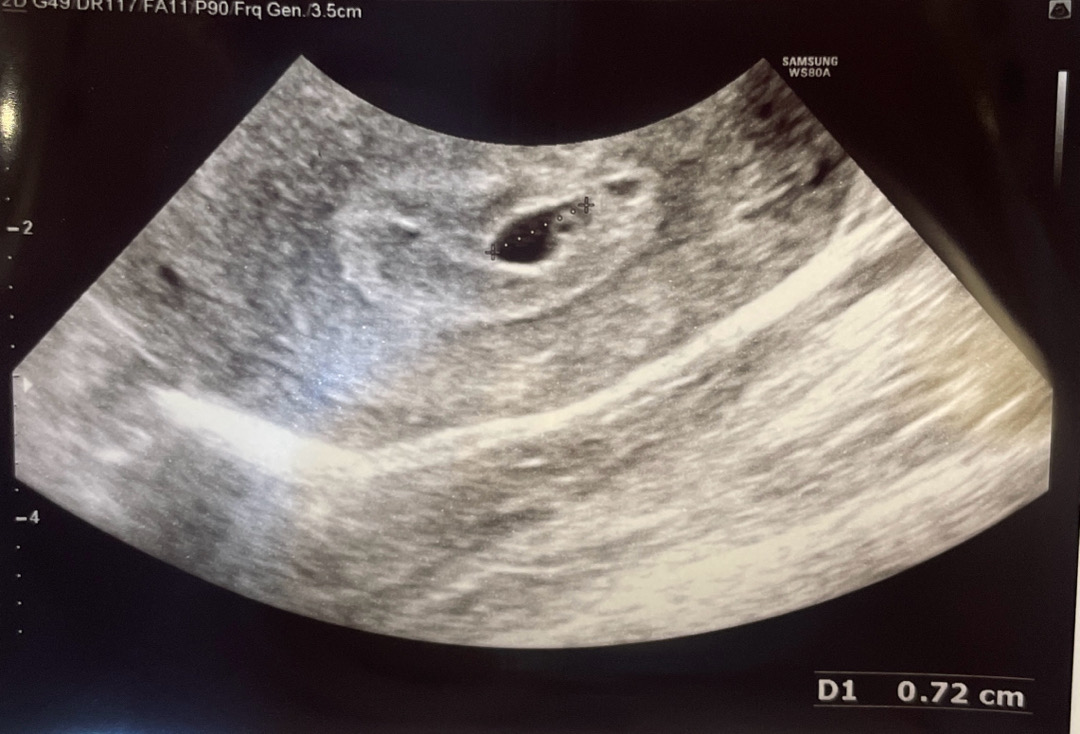

어제 밤부터 갈색출혈 있다가 오늘 갑자기 생리처럼 흘러서 너무 놀라서 바로 병원 왔는데 아기집은 7mm (3일전보다 1미리 커짐) 여서 사실 막생 기준으로는 많이 작아요 ㅜ 아기 심장소리는 아직 못들을거같다 해서 일주일 뒤에 와서 듣자고 지금은 어떻게 더 판단할 수 없다고만 이야기해주셨어요 눈물이 왈칵 쏟아지려고 하는걸 꾹 참고 주사 맞았는데 일주일 잘 버틸 수 있는 용기와 믿음이 너무너무 간절하네요.. ㅜ